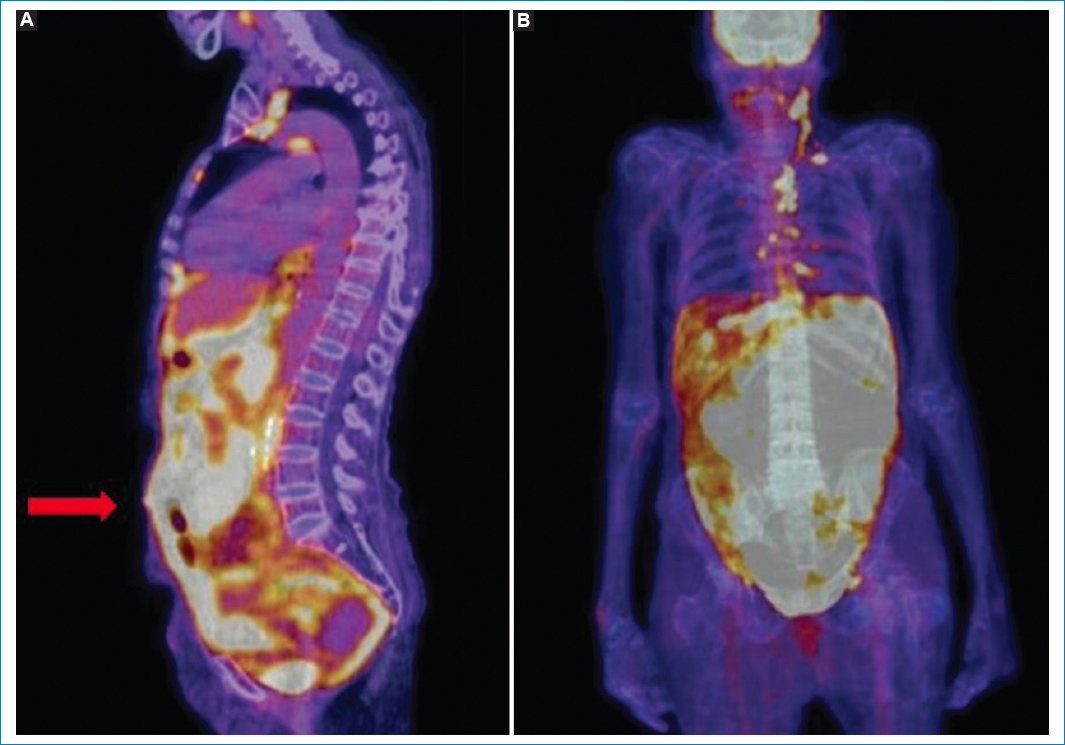

Figura 12. Imágenes coronales de fusión PET-TC (A y B) y MIP de PET (C) de un caso de LP. Como hallazgos acompañantes se evidencian múltiples adenomegalias hipermetabólicas en diferentes niveles ganglionares supra- e infradiafragmáticos (flechas).

Figura 13. Imagen sagital en MIP de PET-TC que pone de manifiesto el hipermetabolismo de la médula ósea en un caso de linfoma con compromiso ganglionar múltiple y peritoneal.

Según Cabral et al.11, el patrón más frecuente de presentación de la LP consiste en la observación del omental cake hipermetabólico, con conglomerados ganglionares múltiples (Fig. 15). El compromiso peritoneal aislado, sin afectación ganglionar, es extremadamente inusual33.

Figura 15. Patrón más frecuente de presentación de la LP, con compromiso difuso peritoneal hipermetabólico (omental cake, flecha) y adenomegalias múltiples; hallazgos evidentes en las imágenes de fusión PET-TC en sagital (A) y coronal (B).